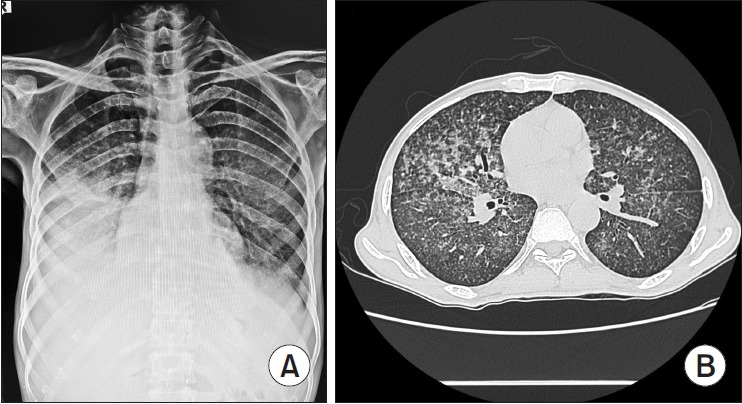

Miliary Tuberculosis Associated with Klebsiella pneumonia: Managing the Double Whammy of Antimicrobial Resistance.

伴有克雷伯氏菌肺炎的睫状体结核病:抗菌药耐药性的双重打击。